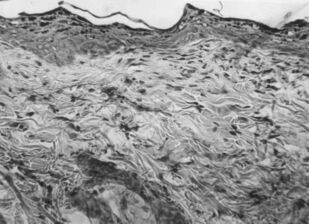

Лишай Видаля: экспериментальное и клиническое применение ультрафонофореза флюоцинолона ацетонида

Монография предназначена для врачей дерматовенерологов, физиотерапевтов, врачей общей практики, студентов выших медВУЗОВ для эффективного и обоснованного применения метода ультрафонофореза флюоцинолона ацетонида у пациентов с простым хроническим лишаем (лишаем Видаля, ограниченного или очагового нейродермита).